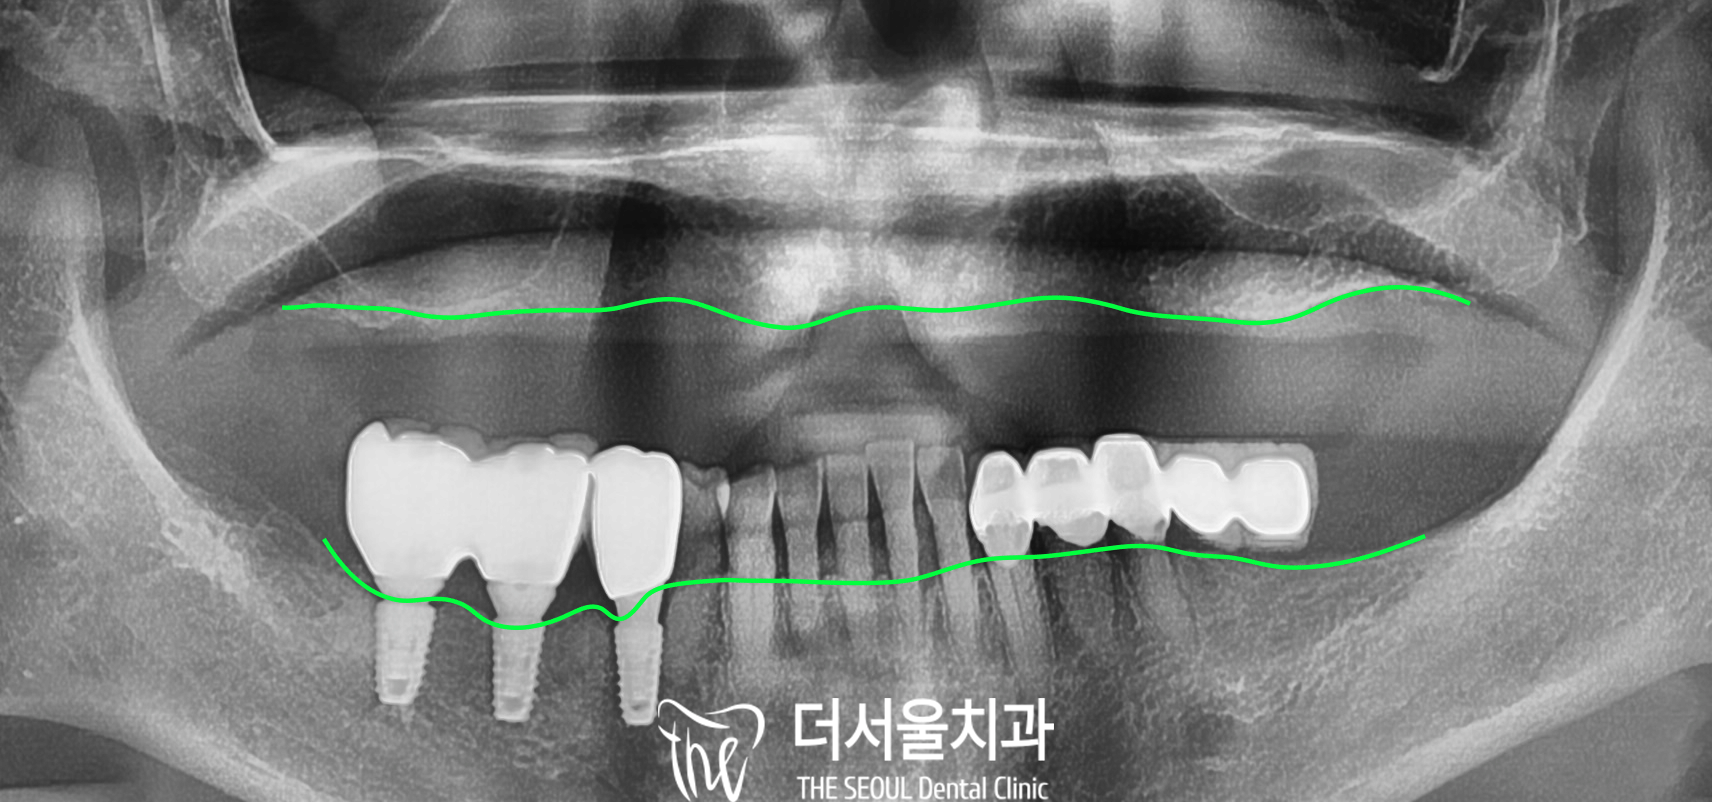

먼저 초진 사진을 보면

전혀 없는 치아를 볼 수 있습니다.

디지털 엑스레이로 자세하게

살펴보았습니다.

오랜 틀니 생활로 흡수된

치조골들을 확인할 수 있는데요.